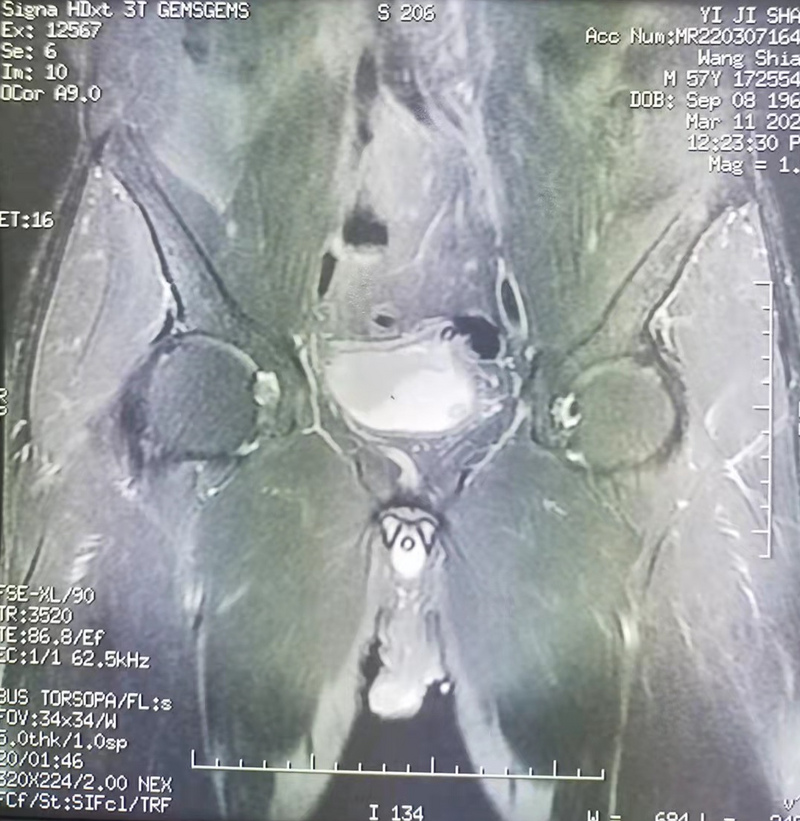

術(shù)前核磁共振

家住當涂縣60歲的男性患者周軍(化名),在外院已確診“浸潤性膀胱癌”。因疫情原因去不了外地治療,患者及其家屬萬分焦慮,遂來我院就診?;颊呤罩稳朐汉螅谀蛲饪茍F隊對其進行全面檢查,患者手術(shù)指征明確,無明確手術(shù)禁忌癥,科主任鄭奇?zhèn)?、副主任王龍信組織全科認真分析討論,結(jié)合該疾病的國內(nèi)外治療進展,制定了合理的手術(shù)方案,即腹腔鏡下膀胱根治性切除+盆腔淋巴結(jié)清掃+回腸代膀胱術(shù)。經(jīng)過充分的術(shù)前準備,手術(shù)當天,在麻醉手術(shù)科及普外科密切配合下,泌尿外科團隊順利完成手術(shù),術(shù)中解剖清楚,未損傷鄰近器官及血管?;颊咝g(shù)后在科室的精心護理下,無明顯并發(fā)癥發(fā)生,康復(fù)良好,順利出院。術(shù)中切除下的標本病理檢查結(jié)果為浸潤性膀胱癌,前列腺緣、輸尿管殘端、淋巴結(jié)均陰性。